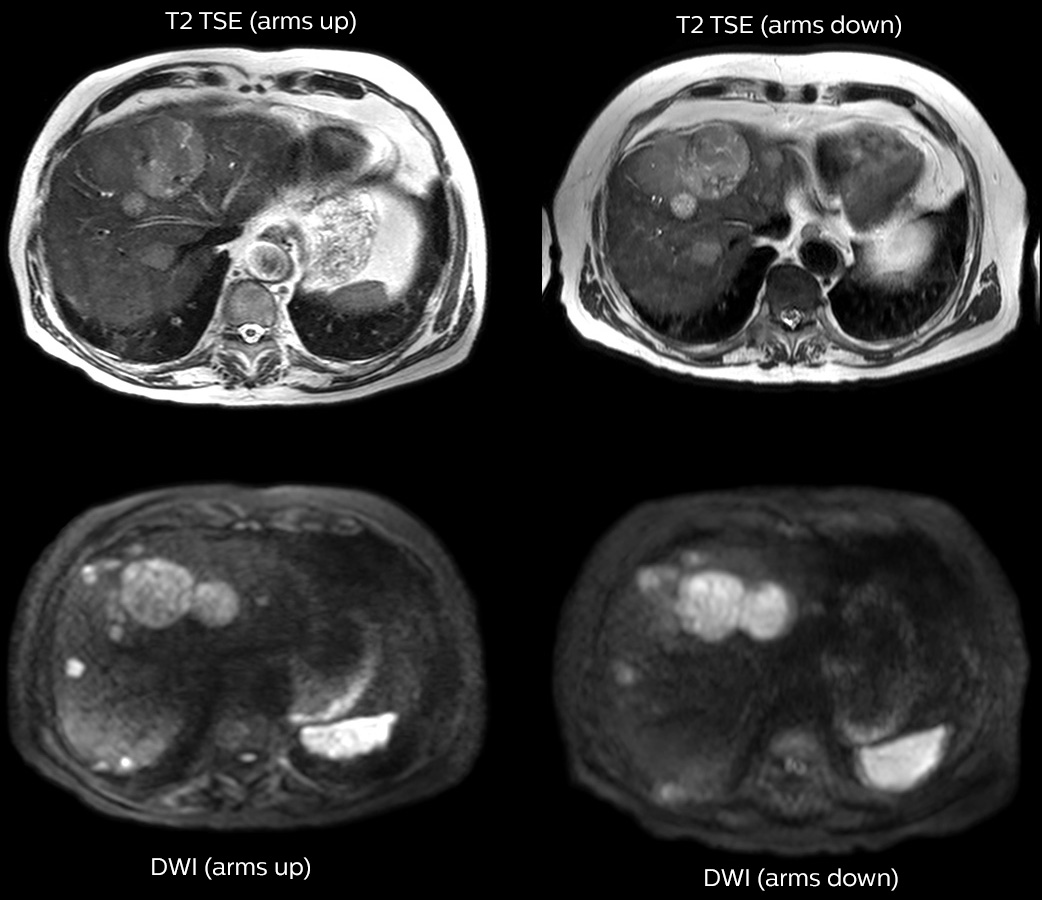

Dr. Kukuk scans an increasing number of liver patients in an arms-up position using the integrated Posterior coil and a special positioning device. “By placing the patient’s arms up, the field of view in the right-left direction can be smaller so that a right-left preparation direction can be used to cut down the scan time,” he explains. “We can use high dS SENSE factors for TSE imaging, so we can shorten the echo train length. This results in a faster scan than arms-down T2 TSE and the images show high anatomical detail.”

“For DWI, the high dS SENSE factor allows using a shorter TE so we get higher signal and fewer susceptibility artifacts, which means less distortion of diffusion weighted images. Of course, with higher dS SENSE factors and the shortening of the TSE factor in T2-weighted imaging, we can drastically cut down the complete examination time. So, with arms-up we get faster images, less distortion in DWI and less blurring on T2-weighted images. Almost all patients tolerate the arms-up scanning well.”

“We get fast images, less distortion in DWI and less blurring on T2-weighted images.”